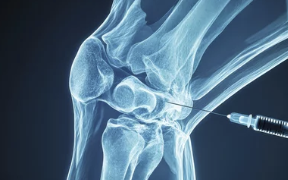

| 연골주사(히알루론산) | 관절 내 윤활 작용 → 마찰 감소, 통증 완화 |

| 고분자 히알루론산 주사 | 점도가 높아 지속시간 연장, 관절 내 환경 개선 |

| PRP (자가혈 재생 주사) | 연골 재생 유도 및 염증 억제 효과 있음 |